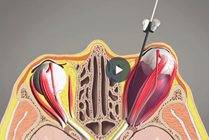

Nasal Turbinate Hypertrophy

Turbinate hypertrophy, inferior turbinate hypertrophy, and nasal turbinate hypertrophy are all descriptions of a similar condition where the tissue on the lateral (outside) walls of the nose are too large, causing nasal obstruction.